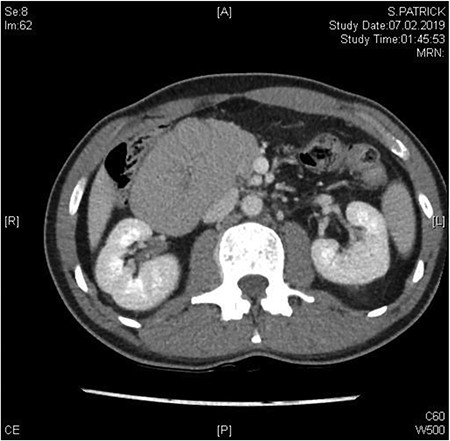

A 37-year-old patient presented with acute abdominal pain which was colicky in nature and accompanied by nausea and repeated vomiting. Physical examination showed tenderness in the right lower abdomen and guarding in all four quadrants. There was no history of previous abdominal surgery. A computed tomography (CT) scan revealed the mechanical obstruction of the small bowel and the suspicion of a pre-existing paraduodenal hernia in the right upper abdomen (Figs 1 and 2). Fortunately, the patient’s condition improved significantly following the administration of analgesia, and the initial conservative treatment was continued. An X-ray with oral contrast agent enhanced the suspicion of a right-sided paraduodenal hernia. As the patient was now pain free, we scheduled an elective diagnostic laparoscopy 3 weeks later.

Between the head of pancreas and the lower edge of the liver, an oval-shaped, clearly defined convolution of small intestine loops measuring ~9.5 x 6.5 cm was visible. The duodenum could not be followed as expected—there is no duodenal part crossing the vessels to the left

In the coronal plane, in addition to the suspicion of an internal hernia, a short intussusception was also suspected. Furthermore, this level shows that the herniating small intestine is located on the right, while the left side of abdomen appears empty